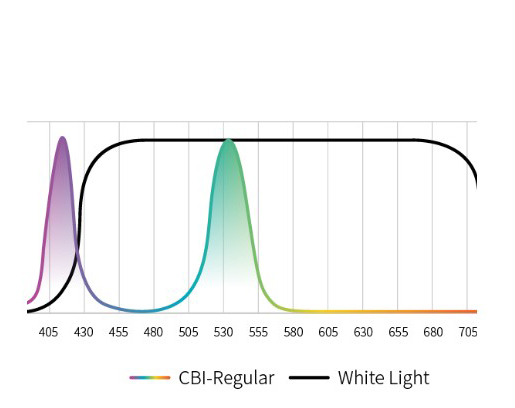

Три режима оптической хромоэндоскопии

Оснащен 4 светодиодными источниками света высокой яркости с независимым управлением, обеспечивающими многоспектральный режим окрашивания «белый свет + 3 спектра CBI». Спектральное окрашивание может повысить визуальный контраст между нормальной тканью и повреждениями, тем самым улучшая выявляемость небольших повреждений. Технология оптического окрашивания (CBI) – удобный и эффективный инструмент для выявления раннего рака, опухолевых и воспалительных процессов.

CBI regular позволяет легко выявлять поражения слизистой оболочки и подчеркивать распределение подслизистых сосудов. |  |

Три режима оптической хромоэндоскопии (CBI). Многоспектральная визуализация с 4 светодиодами высокой яркости:

- CBI regular — визуализация слизистой и подслизистых сосудов.